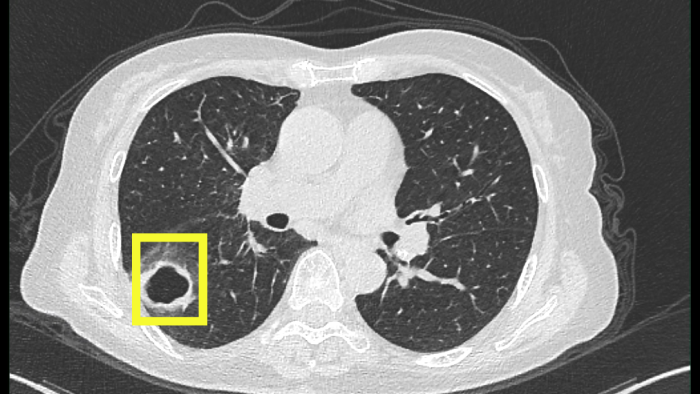

最開(kāi)始以為只是普通感冒,但柴阿姨自行吃藥后并沒(méi)有好轉(zhuǎn)。感到焦慮的柴阿姨便到當(dāng)?shù)蒯t(yī)院就診,經(jīng)肺部CT檢查發(fā)現(xiàn),肺部出現(xiàn)空洞病灶。

當(dāng)?shù)蒯t(yī)院認(rèn)為有可能是肺結(jié)核,柴阿姨忐忑不安地來(lái)到衢州市人民醫(yī)院(溫州醫(yī)科大學(xué)附屬衢州醫(yī)院)感染科就診。

迷團(tuán)終于解開(kāi),原來(lái)引起柴阿姨肺部空洞的“罪魁禍?zhǔn)住辈皇欠谓Y(jié)核,而是真菌感染。

該患者是以咳嗽伴肺部空洞性病灶來(lái)就診的,最常見(jiàn)的病因是結(jié)核分枝桿菌引起的肺結(jié)核,但做了結(jié)核的相關(guān)檢查均未提示肺結(jié)核。而當(dāng)常規(guī)的檢驗(yàn)技術(shù)未發(fā)現(xiàn)病原菌時(shí),氣管鏡檢查及肺泡灌洗液的宏基因組測(cè)序就非常重要,可以讓患者少走很多彎路,使診斷及時(shí)明確,讓患者得到精準(zhǔn)治療。

尖端賽多孢菌感染常常累及呼吸道,可有咳嗽咳痰、發(fā)熱、咯血等癥狀。在肺部感染中,尖端賽多孢菌感染鑒別較為困難,且其感染的影像學(xué)與其他感染非常相似。當(dāng)普通抗感染效果不佳時(shí),要警惕真菌感染。